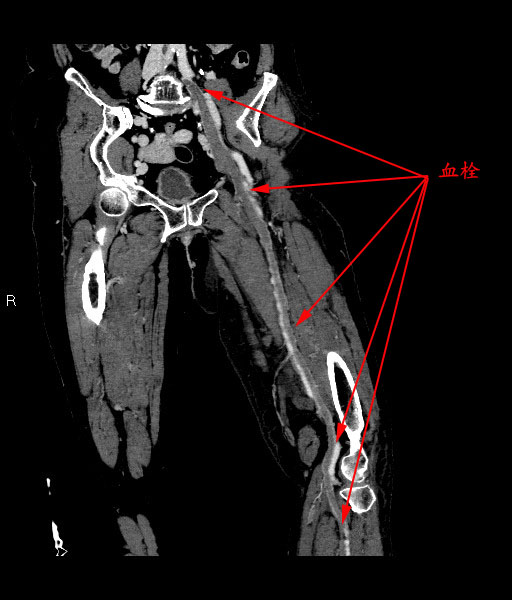

(CTV重建图示左下肢深静脉全程血栓)

经祁家祥主任医师介入团队对该患者病情进行分析、讨论,结合患者的临床症状、体征、实验室检查及影像检查,认为该患者属于亚急性期,可以采用一站式腔内治疗方法,涵盖下腔静脉滤器置入术(IVCF)、经皮机械性血栓清除术((PMT)、经皮腔内血管成形术(PTA)、经导管接触性溶栓治疗术(CDT)和支架植入术。该治疗方法可以帮助患者迅速恢复血流,缩短病程,提高管腔完全再通率,避免或减少静脉瓣膜粘连,降低瓣膜功能不全和血栓复发发生率,尽量阻止病程进入慢性期和后遗症期。